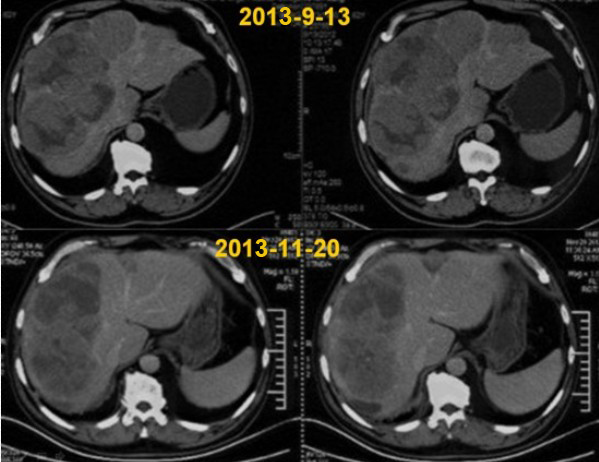

许华林先生是新加坡某知名品牌在中国地区的负责人,由于工作繁重加之饮食不规律,在2013年7月因胃部疼痛被查出患有胃窦癌伴随多发肝转移。许华林的精神食欲极度下降,腹部憋胀频繁发作,体重下降了6公斤。由于治疗耽误和发现较晚,胃癌晚期。手术治疗无法切除,打了一次化疗,许华林的副反应强烈,没有继续进行化疗。

经过1个疗程的WB-1无创全身热疗系统治疗,许华林的病情恢复的很快。他的精神和食欲明显缓解,腹部憋胀得到缓解,肝部转移得到控制,体重增加了4公斤,预期可以达到长期的带瘤生存。